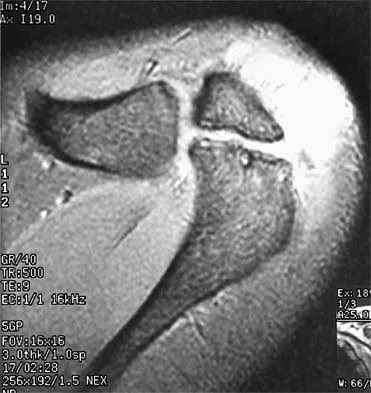

Figures 49a and 49b show MRI scans of the shoulder. What is the most likely diagnosis?

Explanation